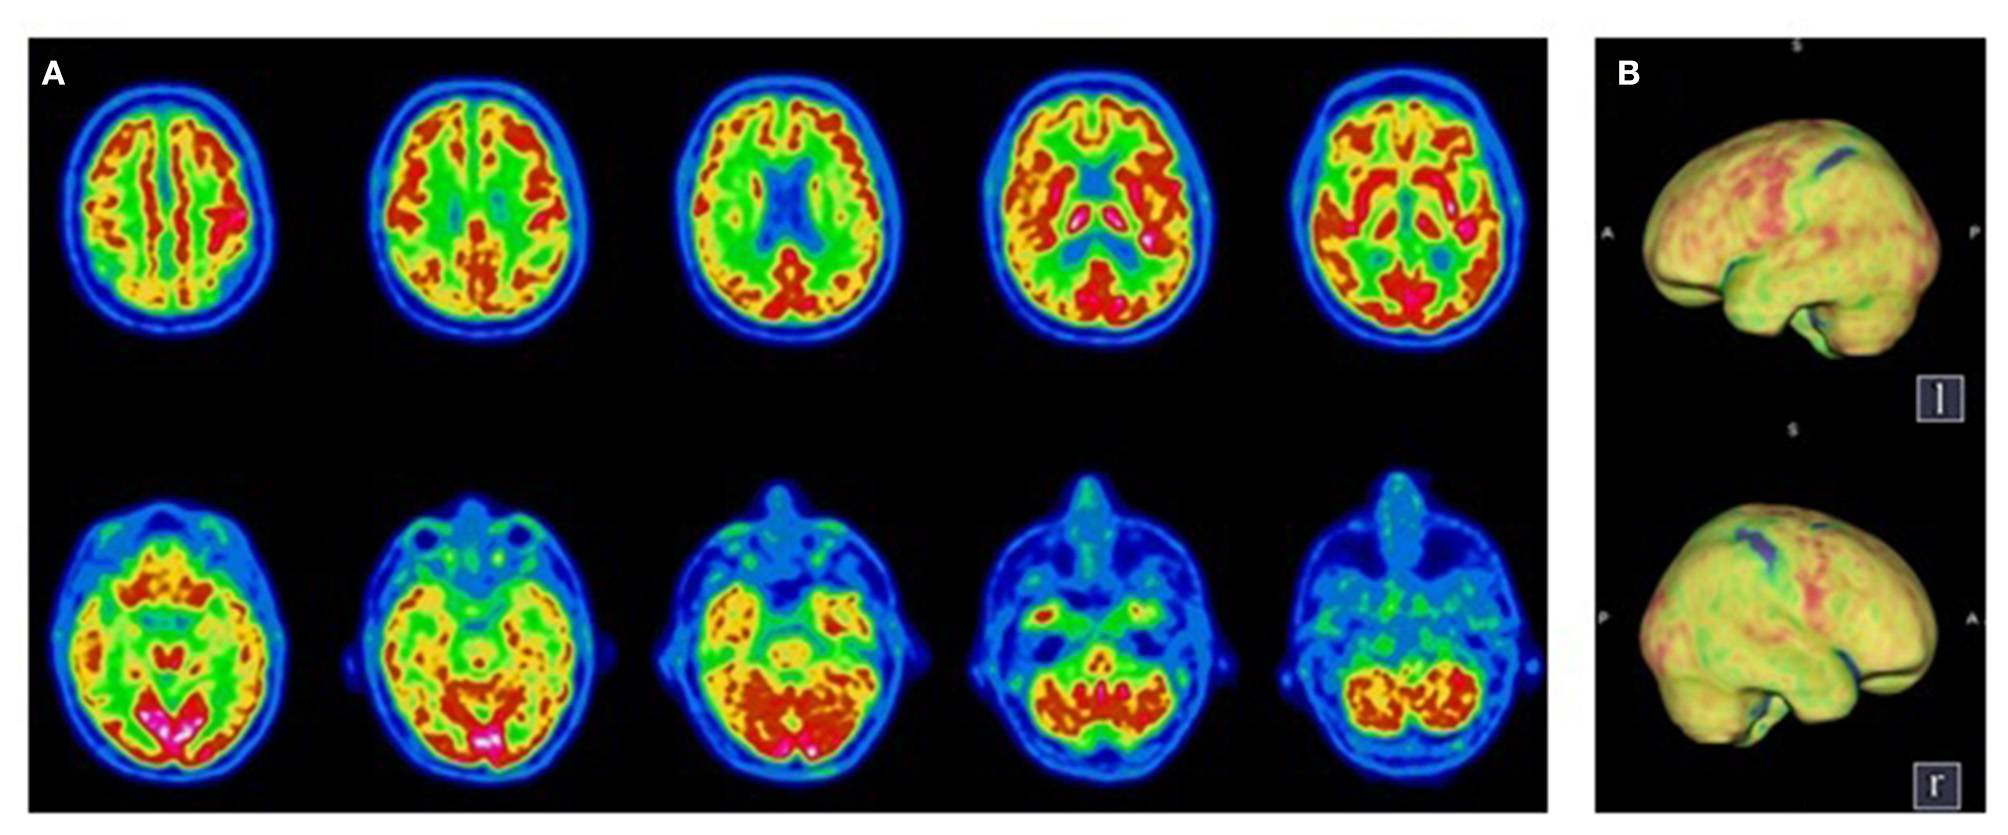

Figure 2

Transaxial (A) and Volume Rendered Brain (B)18F-FDG PET. Diffuse cortical hypometabolism predominant in the right hemisphere, with a preservation of the primary sensorimotor areas. Normal metabolism of the sub-cortical structures and the cerebellum.

A 61-year old patient without known comorbidities was admitted to the ICU with severe ARDS due to SARS-CoV-2 infection and needed endotracheal intubation for 35 days with extracorporeal membrane oxygenation due to multiple complications. He received hydroxychloroquine and azithromycin for 5 days and one dose of tocilizumab. After 65 days, the sedation was withdrawn and the clinical evaluation 48 h later showed a pathological awakening with reduced behavioral evidence, severe dysfunction of the swallowing pattern with discoordination of the swallow motor circuit, and facial akinesia. According to the French version of the Coma Recovery Scale-Revised, the patient was classified as being in a minimally conscious state minus (MCS-) with no response to the command (Table 1), while the MBT-r assessment, considered the patient as presenting with clinical cognitive motor dissociation with the presence of tenuous motor signs (i.e., onset of visual pursuit on the vertical plane, and spontaneous intentional distal movements) not taken into account by the CRS-R, yet deemed as indicators of preserved cognitive abilities. A routine electroencephalogram (EEG) ruled out a non-convulsive status epilepticus, showing a moderate encephalopathy. Brain MRI was unremarkable. The electroneuromyography confirmed a critical illness polyneuropathy. A lumbar puncture could not be performed due to bilateral pulmonary embolism. A brain 18F- FDG PET showed a moderate hypometabolism in the frontal, temporal and parietal regions, sparing the motor, and pre-motor cortex (Figure 2). The neurological symptomatology improved gradually, the patient regained his ability to display overt motor behavior and responded systematically to commands, thus reaching the CRS-R criteria for recovery of consciousness. The overall functional/cognitive improvement confirmed the preserved cognitive abilities as expected in CMD condition and the patient was transferred to a neuro-rehabilitation clinic, 105 days post-admission with a Glasgow Outcome Scale of three (indicating severe disability). He underwent neurorehabilitation for another 69 days obtaining a Glasgow Outcome Scale of 4 (indicating moderate disability) and was able to return home.

Consistent with these data, our hypothesis is that for the two patients, SARS-Cov-2 induced functional impairment in strategically localized areas of the executive motor network (i.e., frontal, pre-frontal). Indeed, the brain 18F-FDG PET in these patients showed a diffused hypometabolism, sparing the motor and pre-motor cortex but affecting the associative areas responsible for the integration of motor initiation and coordination, explaining the clinical picture.